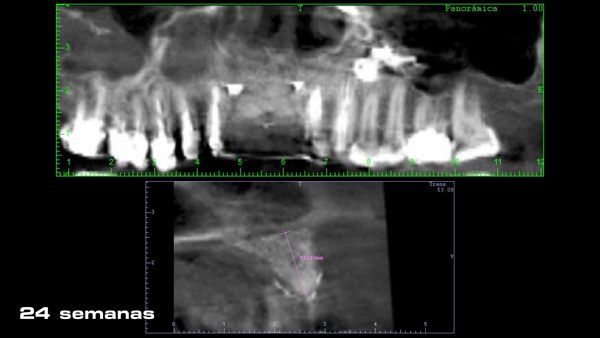

Uma vez que a membrana foi completamente fixada, o retalho foi mobilizado para permitir o fechamento primário livre de tensão. O retalho foi suturado em duas camadas: primeiro, as suturas horizontais em colchoeiro e, depois, as suturas simples para fechar as bordas do retalho (Figura 10). As suturas simples foram removidas 14 dias após a cirurgia e as suturas em colchoeiro horizontais foram removidas três semanas mais tarde. A membrana foi então removida após 25 semanas de cicatrização usando um retalho crestal de espessura total (Figuras 11 a 14).